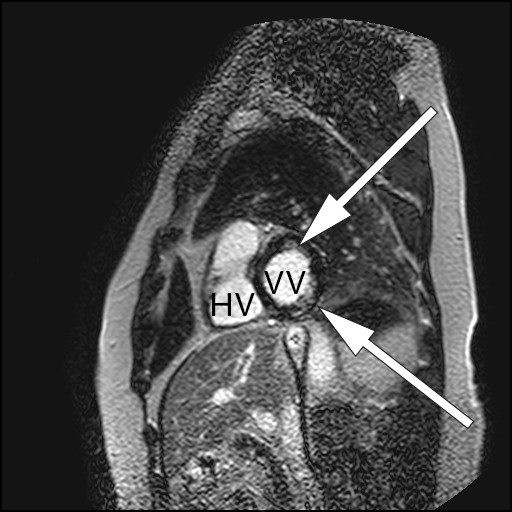

Som ved alle andre undersøkelser er sensitivitet og spesifisitet avhengig av sykdommens prevalens, undersøkelsesmetode og legen som vurderer resultatet av undersøkelsen. Ved MR cor kan man oppdage både inflammatoriske og fibrotiske forandringer som er assosiert med kardial sarkoidose (fig 1–3) (7).

Den aktive, inflammatoriske sykdomsfasen kjennetegnes av økt gadoliniumkontrastopptak ved tidlig undersøkelse og veggfortykkelse som oppstår sekundært til granulomatøs infiltrasjon og ødem (6, 7). Dersom pasientene har utviklet fibrotiske forandringer, vil MR-undersøkelsen vise kontrastopptak ved sen undersøkelse, kalt sen kontrastutvasking (4). Fibrotiske forandringer ved MR-undersøkelse kan være en prognostisk markør som er assosiert med ventrikulære arytmier og mortalitet (4). Fibrosen forekommer som regel ikke i klassiske arterielle forsyningsområder, i motsetning til ved aterosklerotisk hjertesykdom (5). I tillegg vil kontrastoppladningen ved et hjerteinfarkt alltid involvere subendokard (med varierende grad av transmuralitet), mens ved kardial sarkoidose kan kontrastoppladningen forekomme i alle deler av myokard (6).